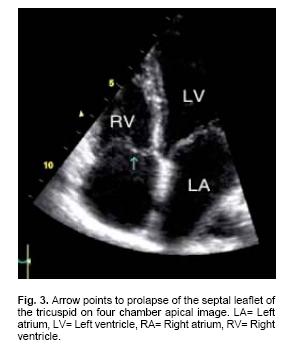

Mitral, tricuspid and aortic valve prolapse was diagnosed by previously established criteria.13,15 Echocardiographic evidence of mitral valve prolapse corresponded to a posterior mitral displacement of at least 2 mm during late systole or a 3 mm displacement throughout systole on M–mode tracings, which was confirmed by billowing of one or both mitral leaflets superior to the plane of the mitral annulus in two–dimensional parasternal long axis views. Pulmonary valve prolapse was defined as the bowing of one or more leaflets into the right ventricular outlet.

Mitral valve prolapse was found in 21 patients (95.5%) of Group I and in 32 (72.7%) of Group II (p = ns, Figs. 2a, b). Tricuspid valve prolapse was detected in 18 (81.8%) patients of Group I and in 26 (59.1%) of those in Group II (p = ns, Fig. 3). Aortic valve prolapse was found in 5 patients (22.7%) of Group I and in 5 (11.4%) of Group II (p = ns, Figs. 4a, b). Furthermore, pulmonary valve prolapse was found in 10 patients (45.5%) of Group I and in 7 (15.9%) of Group II (p <0.03, Table IV, Figs. 5a, b). In contrast, mitral, tricuspid, aortic and pulmonary valve prolapse was not observed in both control groups (p < 0.001) (Fig. 6).